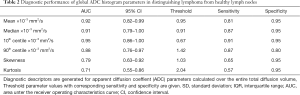

Test results—global ADC

The mean values and SD of tDV and gADC parameters calculated for each patient are shown in Table 1. We found that the mean, median, 10th and 90th centiles gADC values were significantly lower in malignant than in normal lymph nodes. By contrast, ln(tDV), gADC skewness and kurtosis were significantly larger in lymphoma. The gADC SD, IQR, minimum and maximum gADC showed no significant difference between malignant and normal lymph nodes (each P>0.052).

Table 2 shows the performance of the significant gADC discriminators. The order of the diagnostic accuracies of gADC parameters by AUC performance from highest to lowest was: 10th centile, mean, median, 90th centile, skewness and kurtosis. Figure 2 visualises the overlap of gADC parameters between lymphoma and healthy individuals. There was no significant difference of AUC between mean and median gADC, 10th and 90th centile gADC (each P>0.131). Mean gADC AUC was significantly larger than gADC skewness AUC (P=0.032) and gADC kurtosis (P=0.004). 10th centile and median gADC AUC were significantly larger than for gADC kurtosis (each P<0.010). Median and 90th centile gADC AUC were significantly larger than for gADC skewness (each P<0.043). In correspondence to the AUC, the highest Youden index among gADC histogram parameters was calculated for the 10th centile gADC at a threshold of 0.67×10−3 mm2/s, smaller values identifying disease with 91% sensitivity and 95% specificity. A median gADC value less than 0.91×10−3 mm2/s identified disease with 87% sensitivity and 95% specificity. 81% sensitivity and 95% specificity was shown for a threshold mean ADC value of 0.95×10−3 mm2/s. Sensitivity of the 10th centile cut-off was significantly larger than for the mean gADC cut-off (P=0.046). Exemplar maximum intensity projections delineating lymph nodes of a lymphoma patient and a healthy volunteer are demonstrated in Figure 3. Figure 4 visualises the corresponding gADC histograms of lymphoma and healthy nodes of this particular patient (A) as well as the ADC distribution across all study subjects in both groups (B). No gADC parameter showed significant difference between different lymphoma subtypes (each P>0.324).